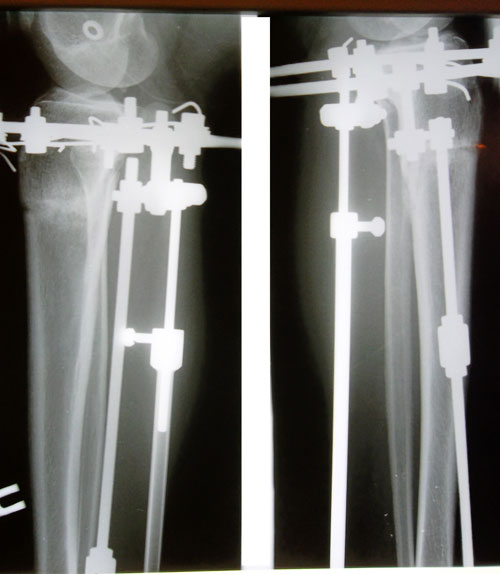

Дата операции 23.07.2014г.

Дата снятия аппаратов 17.11.2014г.

Срок лечения 114 дня.